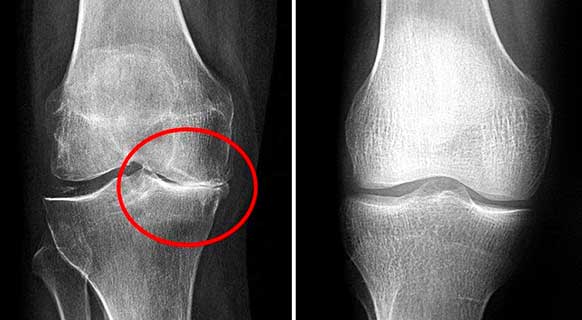

รูปภาพ: ภาพรังสีเอกซ์ของข้อเข่าก่อนและหลังทานแคปซูล Movinix